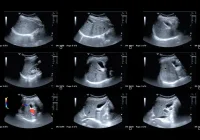

Contrast-enhanced ultrasound (CEUS) has grown from a narrowly licensed tool into a technique with much wider clinical relevance. Initially approved only for focal liver lesions, breast, peripheral arterial system and cardiac imaging, its use has steadily expanded over the past two decades. Clinicians increasingly apply CEUS to a variety of organs and conditions, recognising its advantages over computed tomography (CT) and magnetic resonance (MR) in terms of safety, cost and patient acceptability. CEUS uses microbubble contrast agents that are strictly intravascular, non-nephrotoxic and do not cross the placental barrier, making it especially valuable in vulnerable populations. Despite mounting evidence, controversies persist regarding its application in pregnancy, paediatrics, abdominal trauma, renal cyst evaluation and follow-up after endovascular aortic repair (EVAR). These areas highlight both the promise and the challenges of integrating CEUS more widely into diagnostic pathways.

Blunt abdominal trauma represents one of the most compelling scenarios for CEUS. Standard diagnostic pathways emphasise CT and focused abdominal sonography for trauma, yet CEUS demonstrates significantly higher sensitivity and specificity than conventional ultrasound for detecting organ injuries. It enables assessment of hepatic, splenic, renal, adrenal and pancreatic trauma, correlating closely with CT findings. Its portability allows bedside use and repeated assessments during follow-up, making it especially valuable in emergency settings and resource-limited environments. CEUS is particularly advantageous in paediatric trauma follow-up, where it detects complications such as pseudoaneurysms without exposing children to radiation. Limitations include reduced performance in multi-organ injuries, difficulty with bowel or diaphragmatic lesions, and dependence on operator skill. Regulatory barriers also constrain its integration into major trauma guidelines despite clear clinical value.

Renal cysts provide another area where CEUS has proven useful. Cystic renal lesions are common, particularly in elderly patients, and their classification determines management. The Bosniak system, traditionally based on contrast-enhanced CT, has guided risk stratification for decades but carries limitations related to radiation exposure, interobserver variability and inadequate characterisation of atypical lesions. CEUS offers superior resolution for evaluating septations, wall thickening and vascularity, features that are key indicators of malignancy. Meta-analyses confirm that CEUS achieves high sensitivity and specificity in differentiating benign from malignant cysts. The 2019 update of the Bosniak classification and subsequent European proposals have incorporated CEUS, showing good reproducibility even among less experienced observers when structured reporting is used. CEUS avoids nephrotoxic agents, can be performed without renal function tests and is more cost-effective than repeated CT or MR follow-up. Challenges remain in patients with unfavourable body habitus or poor acoustic windows, but where feasible CEUS offers immediate and accurate lesion characterisation.